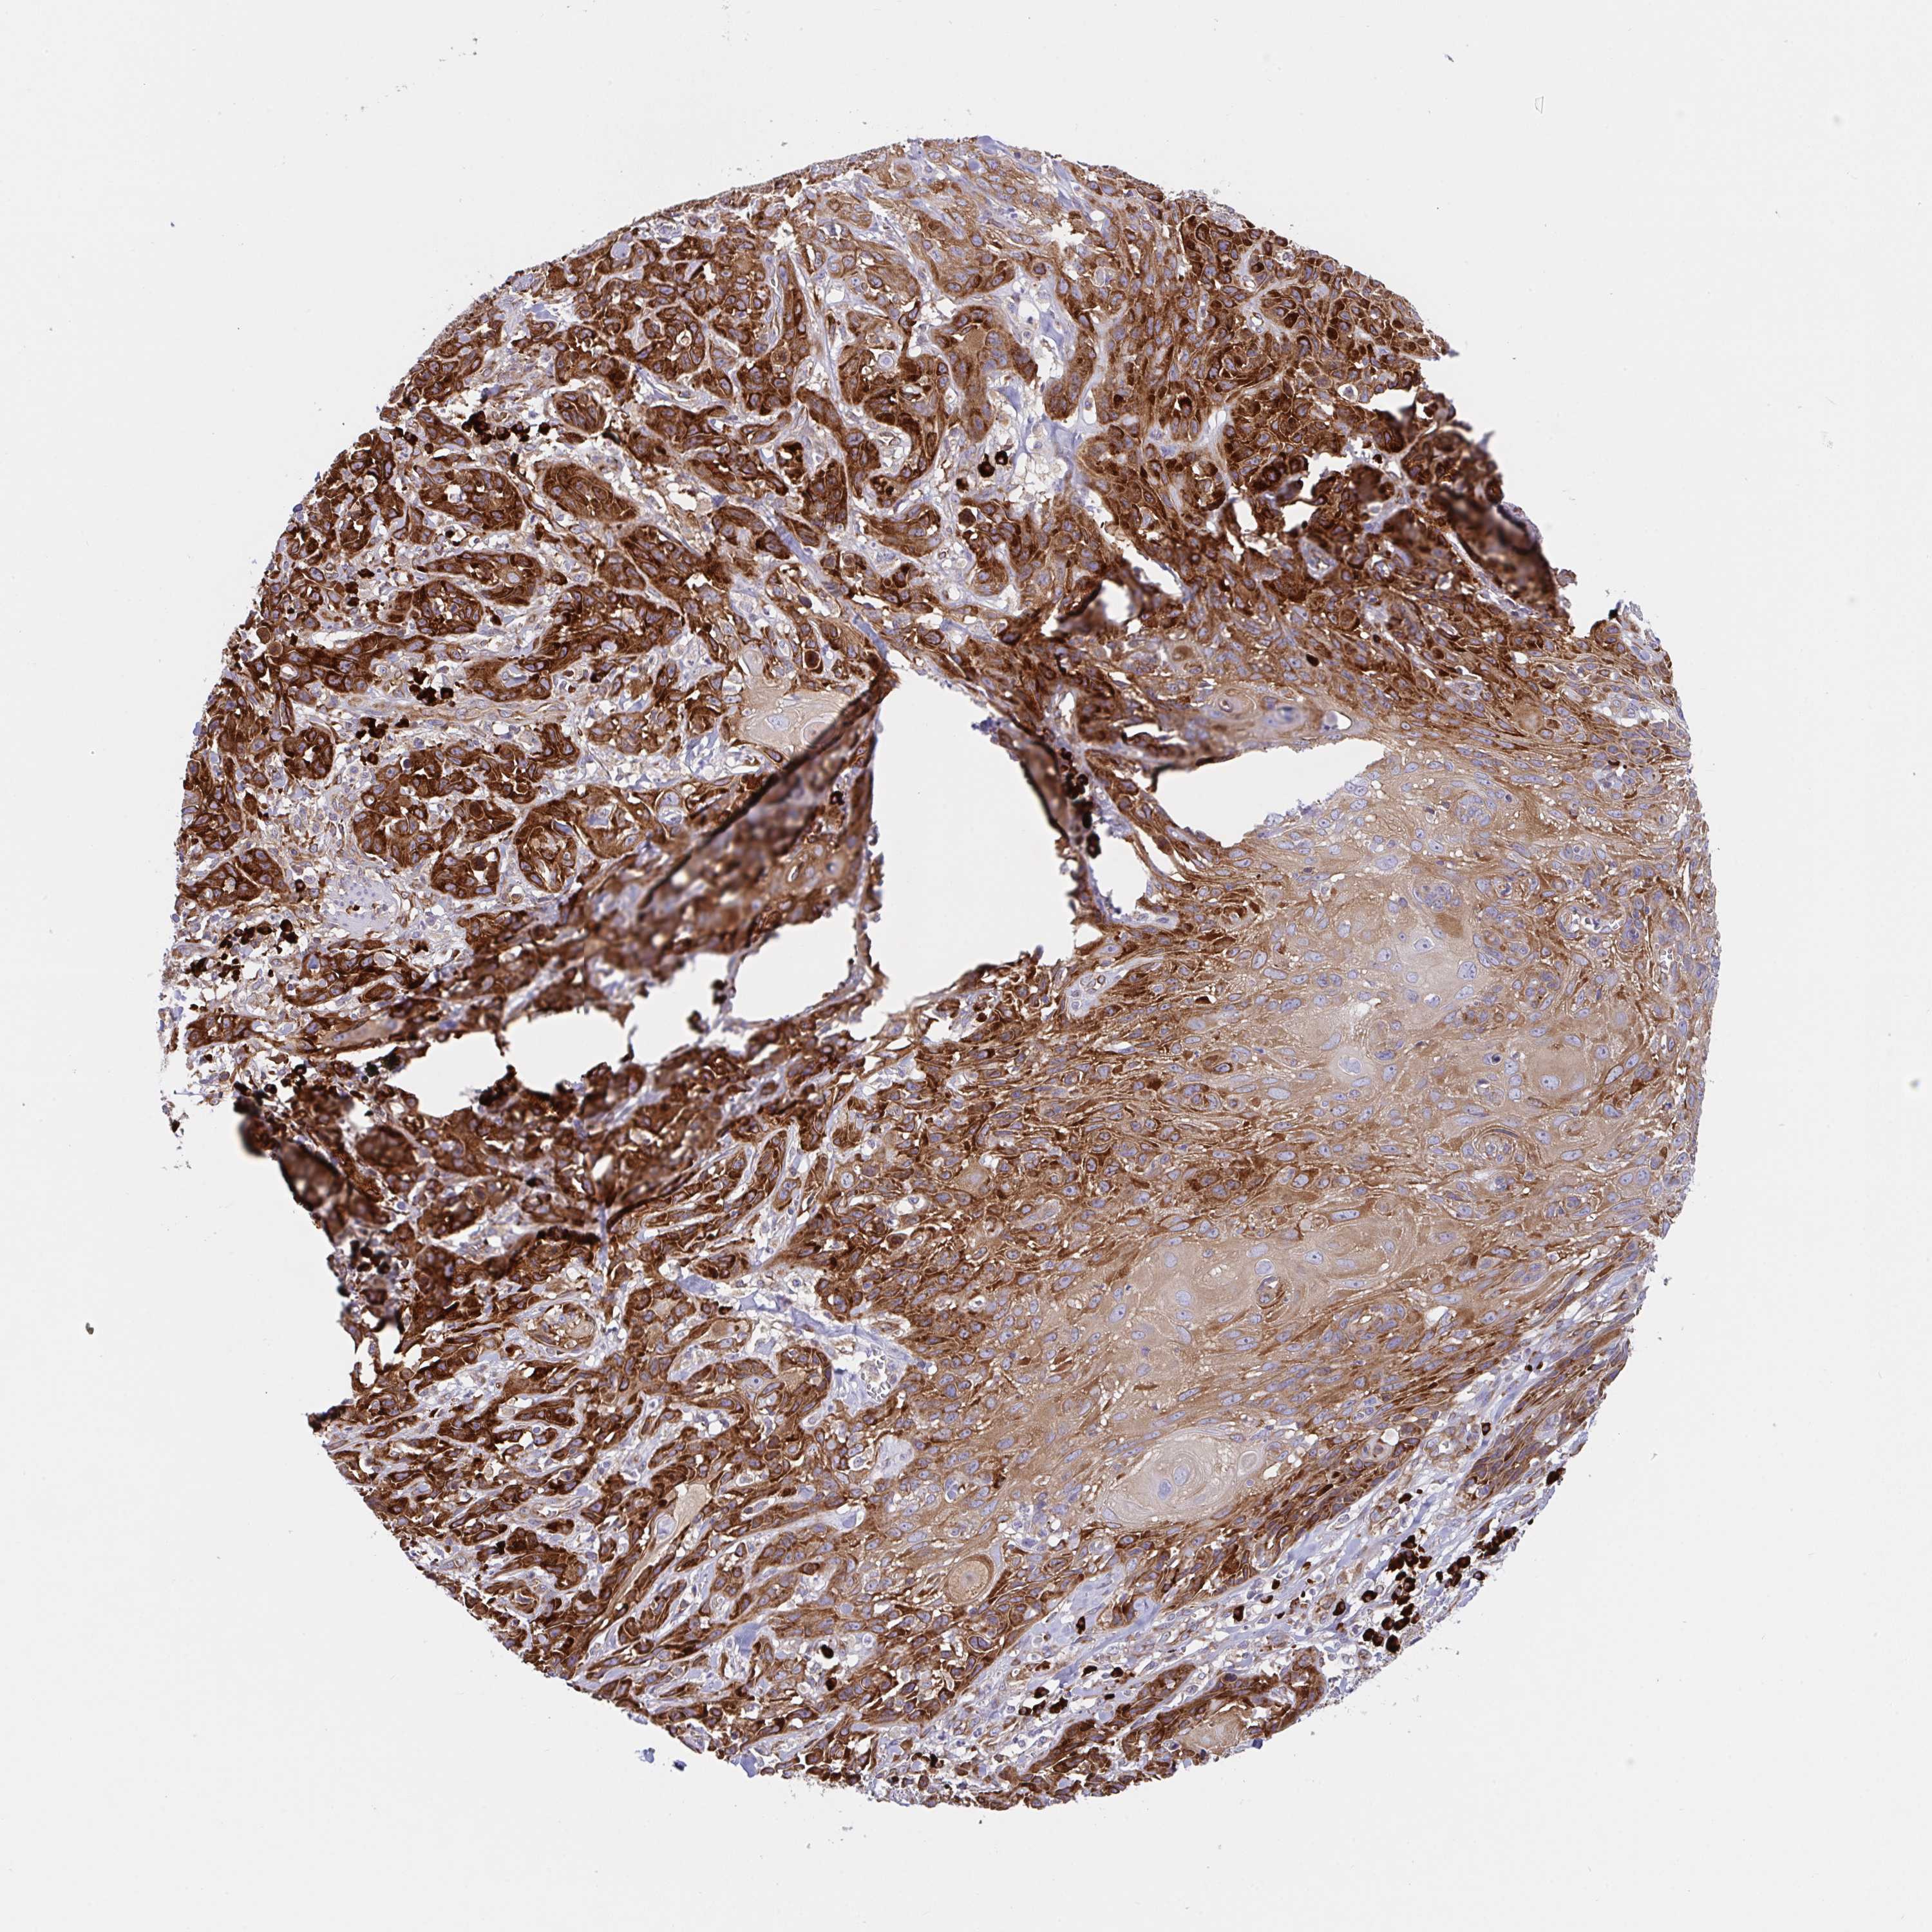

SKIN CANCER - Protein expressioni

A mouse-over function shows sample information and annotation data. Click on an image to view it in a full screen mode. Samples can be filtered based on level of antibody staining by selecting one or several of the following categories: high, medium, low and not detected. The assay and annotation is described here.

Antibody stainingi

Antibody staining in the annotated cell types in the current human tissue is reported as not detected, low, medium, or high, based on conventional immunohistochemistry profiling in selected tissues. This score is based on the combination of the staining intensity and fraction of stained cells.

Each image is clickable and will lead to virtual microscopy that enables deeper exploration of all samples and also displays staining intensity scores, fraction scores and subcellular localization as well as patient and tissue information for each sample.

Antibody HPA038721

Squamous cell carcinoma, metastatic, NOS

Squamous cell carcinoma, NOS